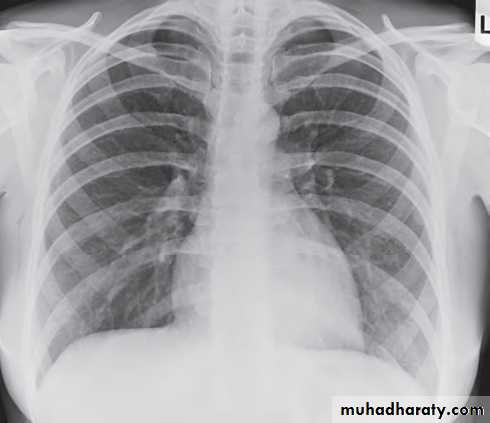

1) CXR

Parts :• 1) Lungs ( Both lung fields )

• 2) Mediastinum

• 3) Chest wall (ribs& soft tissues )

• 4) Diaphragm

• 5) HilaGood CXR = correct diagnosis

• Pleural effusion : collection of fluid within the pleural space. This can be further divided into Transudate , exudate, according to protein content .Other type of fluid collection within pleural space are

• Chest x-rays are the most commonly used examination to assess for presence of a pleural effusion, however it should be noted that on a routine erect frontal chest x-ray as much as 200-500 ml of fluid is

• required before it becomes evident .

blunting of the costophrenic angle

blunting of the cardiophrenic angle

fluid within the horizontal or oblique fissures

eventually a meniscus will be seen, on frontal films seen laterally and gently sloping medially

with large volume effusions, mediastinal shift occurs away from the effusion

• Lateral films are able to identify a smaller amount of fluid ( about75%)as the costophrenic angles are deepest posteriorly posteriorly